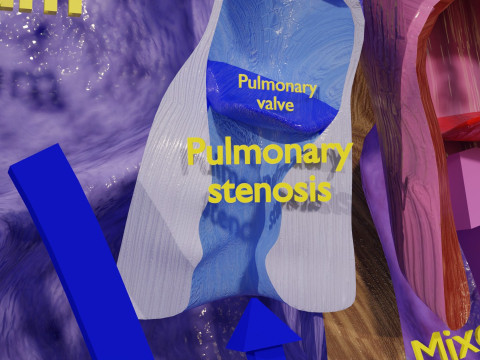

The model meshes include adult circulation versus circulation in Tetralogy of Fallot (TAF), arrow labels and text labels. The blood flow in a patient with Tetralogy of Fallot is outlined in this model. To contrast it to normal blood circulation a separate model of normal circulation is included. The Tetralogy of Fallot (OVER RIDING OF AORTA, PUL STENOSIS, VENTRICULAR SEPTAL DEFECT, RIGHT VENTRICULAR HYPERTROPHY), fossa, ligament teres , venosus, and arteriosus are duly depicted with proper labelling and blood flow directional arrows. Excellent model for teaching, demonstration and knowlegde of human body. The models include both procedural and image textures blend files separately. The texture file include diffuse, roughness and normal png and jpeg based on non overlapping UV maps.